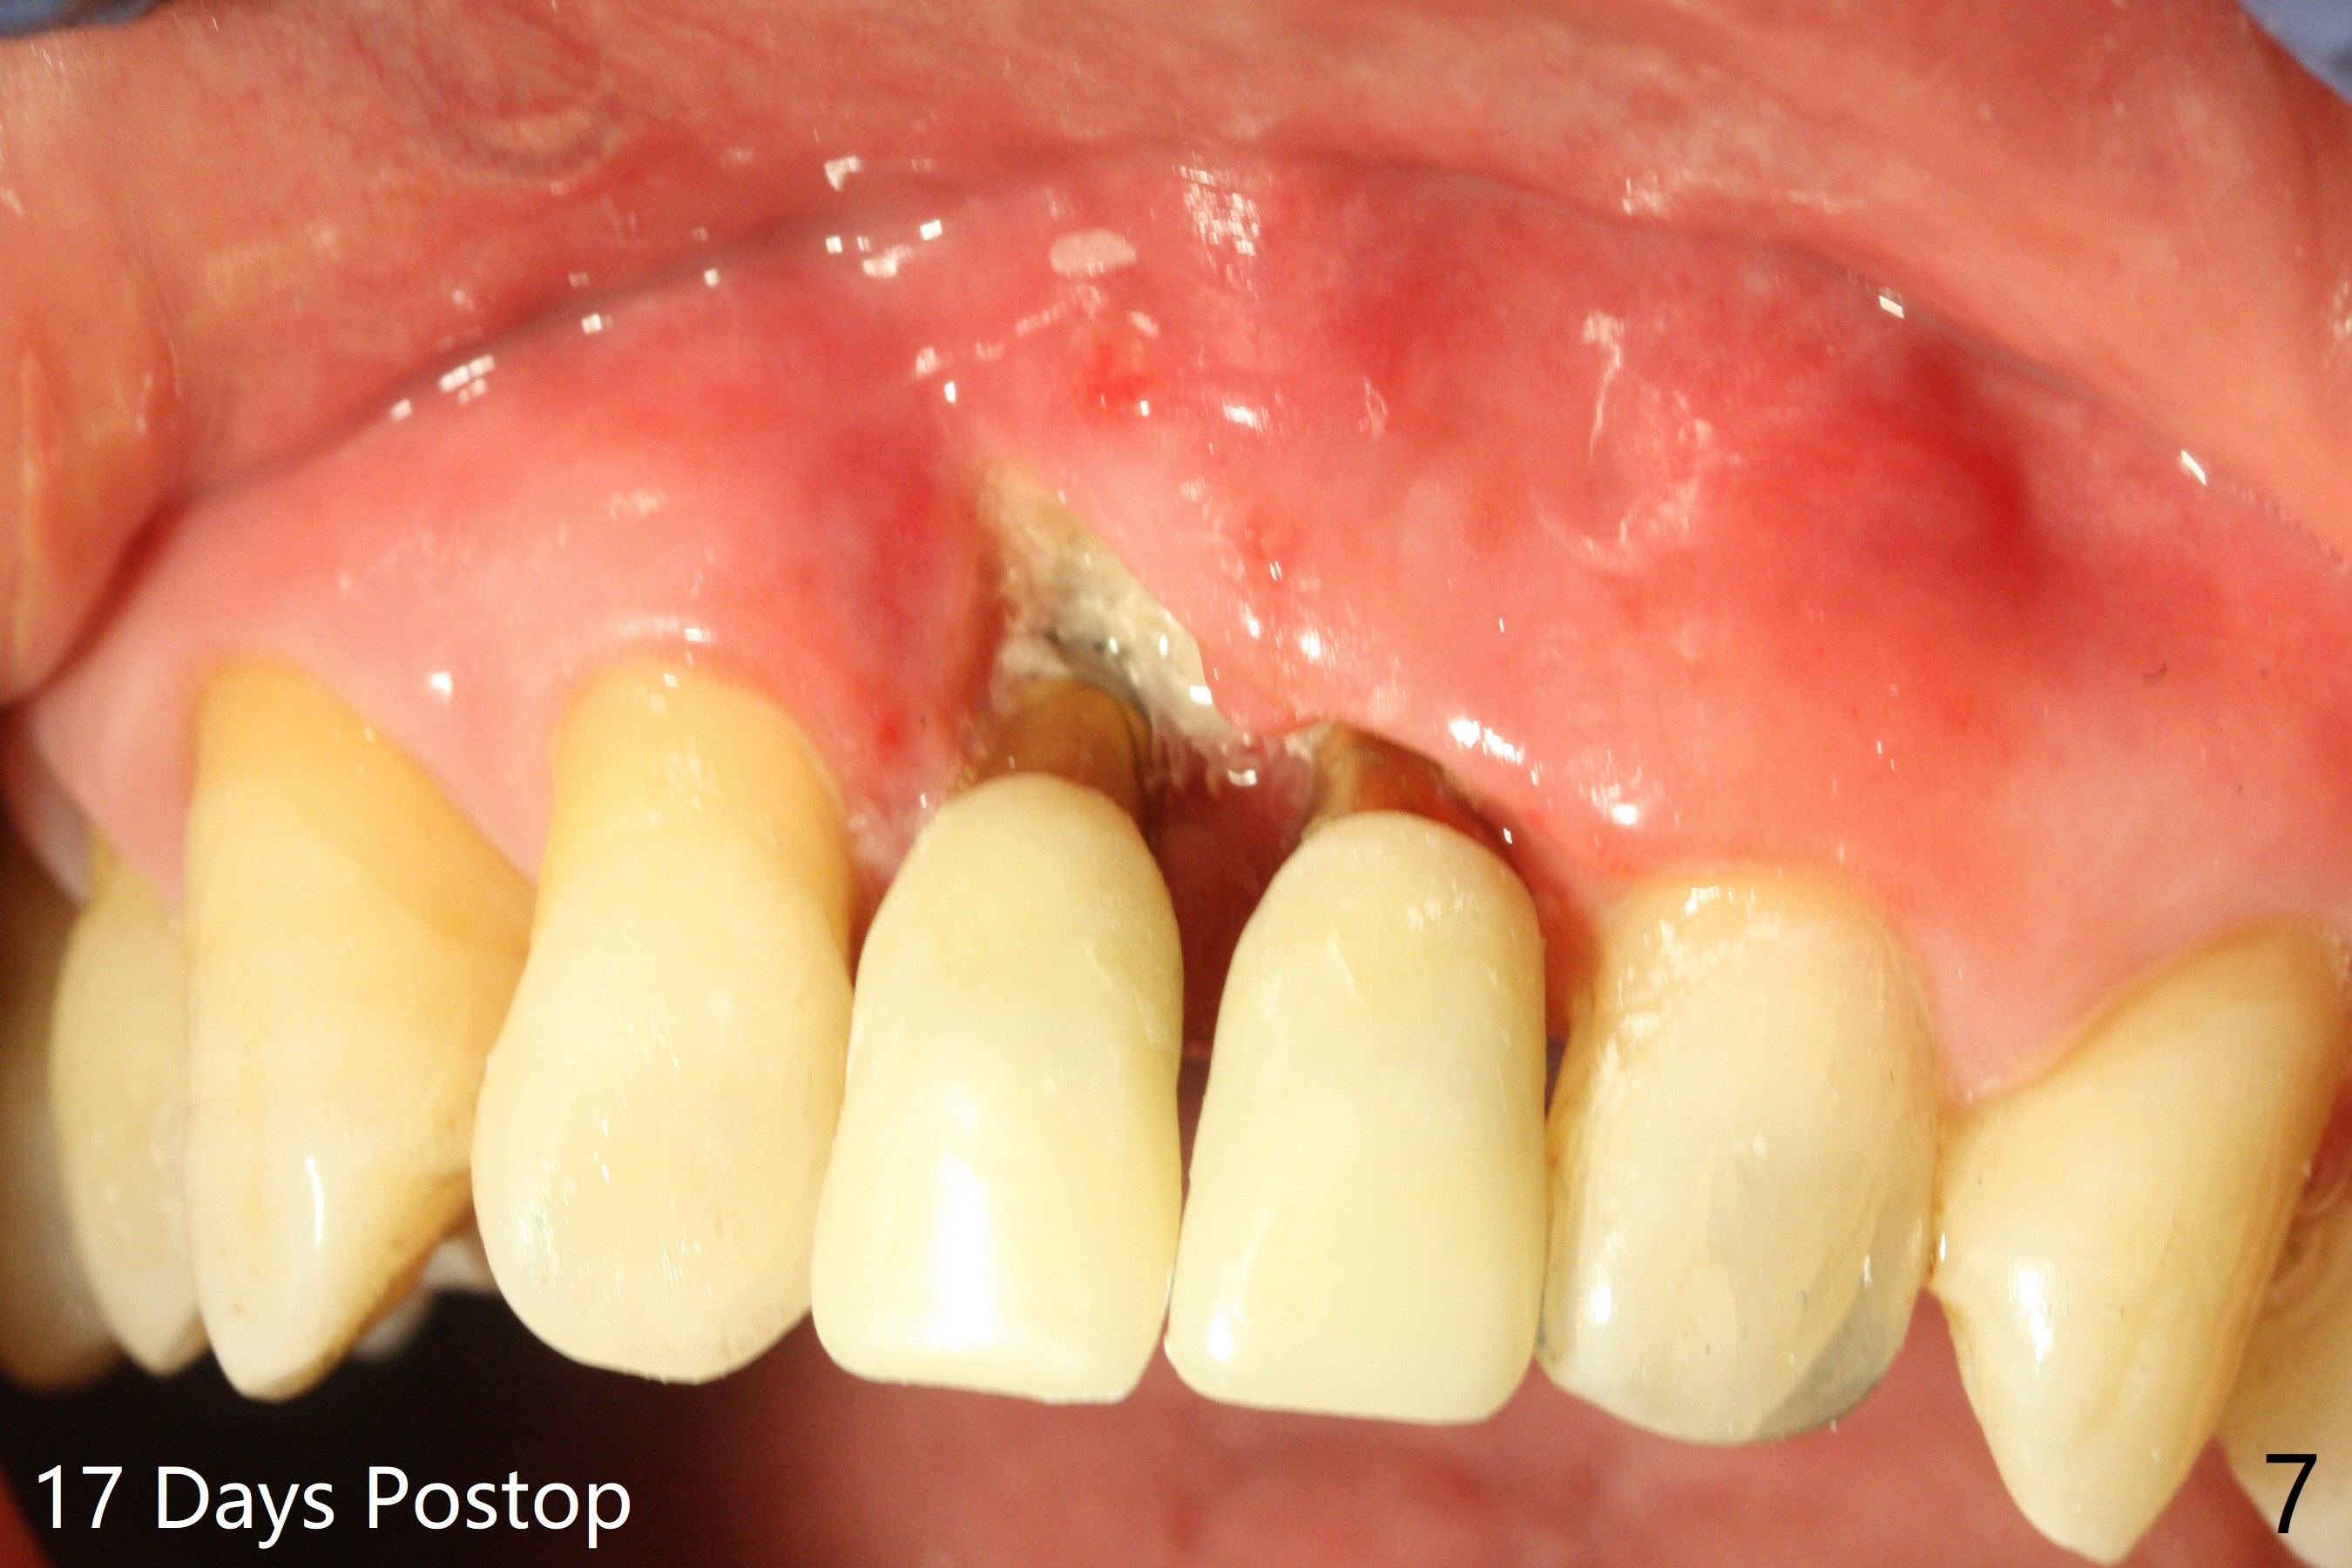

There is no buccal plate at #8 or 9 when the teeth are extracted as well as severe soft tissue defect at #8. Osteotomy is initiated as palatal as possible (Fig.1). When 3.5x13 mm implants are placed initially, the one at #8 is supracrestal (Fig.2 ^). To reduce the chance of peri-implantitis, the implant is placed deeper (Fig.3 (~2 mm implant threads exposed buccally)) with placement of sticky bone around the implants and 4.5x5.5(4) mm abutments (Fig.3 *). The buccal soft tissue defect #8 is repaired with a piece of PRF membrane (Fig.4 *), followed by periodontal dressing. Smaller 2-piece implants (3 mm, IBS) with smaller abutments (4 mm) may further reduce chance of periimplantitis and easy buccopalatal reduction of the abutments for restoration. The periodontal dressing remains stable 7 days postop (Fig.5) because it wraps around the abutments (Fig.6 A). By the time the periodontal dressing gets loose, #8 buccal soft tissue defect should be healing. When breaking-down periodontal dressing is removed 17 days postop, the coronal abutments and bone graft are exposed; after fabrication of provisional crowns (Fig.7), periodontal dressing is re-applied buccally. When the second dressing dislodges 5 weeks postop, the buccal soft tissue appears to reduce (Fig.8). Raising flaps may be less traumatic. A piece of bone graft is being extruded 4 months postop (Fig.9 >). After the abutments change from 4.5x5.5(4) to 4.5x7(3) mm, new temporary crowns are fabricated (Fig.10 (4.5 months postop)). CT shows apparent buccal bone at #8 and 9 (Fig.11,12). How to improve cosmetic?